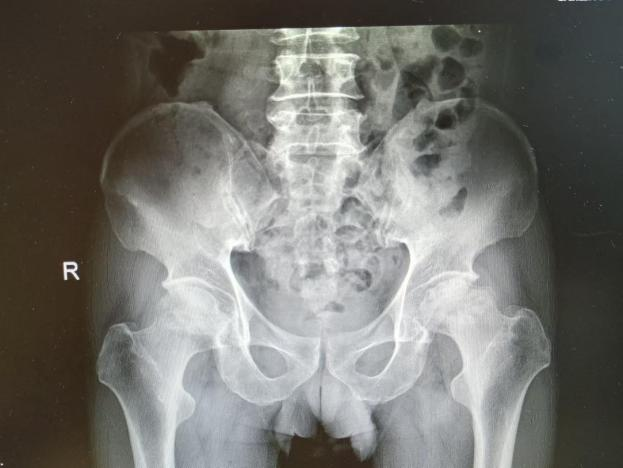

12月17日,贵州航天医院第88次晨读会由我院骨一科主任、副主任医师陈明勇作学术交流,他以“肱骨近端骨折并肩关节脱位的手术治疗”为题,全面讲解了该损伤的手术策略、术中血供保护理念及内侧支撑重建技术等内容,并通过多个典型病例图文资料分享了从损伤机制分析、手术步骤实施到术后随访评估的完整过程与关键细节,为临床处理此类复杂骨折提供了较为全面的技术参考,有助于在手术规划中结合个体情况开展针对性治疗。 贵州航天医院 骨科专家简介 陈明勇 骨一科主任,副主任医师 临床擅长:从事创伤骨科工作约20年,对骨缺损、骨不连、骨肿瘤、肢体畸形等的肢体矫形重建及功能重建,慢性化脓性骨髓炎的根治治疗、糖尿病足的保肢治疗、快速康复理念(ERAS)下的老年骨折的诊治,四肢复杂骨折的诊治,四肢骨折等微创手术治疗具有丰富的临床经验。 2004年毕业于遵义医学院临床专业,曾在中国人民解放军总医院、广西医科大学第一附属医院、上海第六人民医院骨科进修。中国中西医结合学会骨伤科专业委员会横向骨搬移治疗糖尿病足及微血管网再生学组首届委员,遵义市医学会创伤分会常务委员。 瞿 晖 骨科党支部书记,骨二科主任,副主任医师 临床擅长:对骨科的常见病、关节外科、脊柱外科及运动医学疾病的诊治具有丰富的临床经验,熟练掌握骨科手术操作技术。 毕业于遵义医学院临床医学系,2005年前往广州中山大学第一附院骨显微医学部进修学习,2011年前往成都华西医院进修学习,并多次在省内外学习骨科相关知识,是中华医学会骨科分会会员。 赵小锋 中共党员,骨二科副主任,副主任医师 临床擅长:从事骨科临床工作11年,对骨科常见病、多发病诊疗有较为丰富的临床经验,擅长脊柱相关疾病诊断及治疗,尤其是颈、腰、腿疼痛疾病诊断及治疗,擅长胸腰椎骨折微创经皮穿刺内固定术、经皮穿刺椎体成形术、经皮穿刺脊柱内镜下腰椎间盘摘除术、单纯开创腰椎间盘摘除术、腰椎滑脱复位椎间植骨椎融合内固定术、腰椎管狭窄减压融合内固定术及人工髋、膝关节置换术等。 2012年毕业于遵义医学院外科学专业硕士研究生,2019年参加“遵义市115医学人才精英计划”于上海交通大学第一附属医院培训学习,2023年于北京大学第三人民医院脊柱外科进修学习,曾获得遵义市优秀医师荣誉称号。 遵义市手外科第一届委员,遵义市医学会创伤分会第一届委员,遵义市医学会创伤分会第二届委员,贵州省康复医学会第三届脊柱脊髓专业会委员,遵义市医学会烧伤与整形外科学分会委员,发表论文5篇,其中国家级核心期刊1篇,SCI论文1篇,主持市级课题1项并结题,参与市级课题2项。 赵兴东 骨科主任医师 临床擅长:擅长骨科的常见病及各种创伤、四肢骨折创伤修复、骨感染、手足疾病的诊治和手足体表畸形的矫形整复,熟练掌握骨科四肢骨病及创伤的手术操作技术,尤其在四肢关节复杂性损伤、手足外伤、组织缺损创面、难治创面的皮瓣修复方面及平足、高弓足矫形方面及四肢慢性疼痛诊治、康复方面具有丰富的临床经验。 硕士研究生,毕业于遵义医学院临床外科系,2015年前往山东省立医院手足外科进修学习;遵义市医学分会创伤分会第一、二届委员,遵义市手外科医学会第二委届员会常务委员;在省级及省级以上期刊发表文章9篇,参编著作2部,参与主持并完成市级课题1项,参与市级课题2项、省级课题1项。 张艳金 中共党员,骨科副主任医师 临床擅长:从事骨外科工作16年,对复合伤、多发伤的救治、四肢骨干骨折、关节周围骨折、骨肿瘤、骨髓炎等诊治具有丰富的临床经验。 中共党员,硕士研究生,2006年本科毕业于山西医科大学第二临床医学院,2011年研究生毕业于北京军区总医院;在“老年COPD患者合并髋部骨折的诊治”国际合作课题组研究两年,在老年髋部骨折的诊治方面具有丰富的经验,并发表论文6篇;主持遵义市级课题1项,承担遵义医科大学的临床教学工作,获得遵义医科大学优秀带教老师荣誉。编撰有《骨科疾病诊疗精粹》一书,开展2项新技术,编撰地方规范《务川自治县创伤骨科常见疾病诊疗规范》一书。 张俊凯 骨科副主任医师 临床擅长:从事骨科临床工作28年,对创伤骨折、骨感染、骨缺损、骨不连等外科诊治,四肢骨折的微创手术治疗,四肢复杂骨折(如关节内粉碎性骨折、多发骨折等)的损伤控制及手术治疗等具有丰富的临床经验。 1995年毕业于遵义医学院临床专业,2009年前往复旦大学附属医院骨科进修1年。 卢懿明 中共党员,骨科副主任医师 临床擅长:从事骨科工作18年,对创伤骨折、四肢骨折的微创手术治疗、四肢复杂骨折(如关节内粉碎性骨折、多发骨折等)的损伤控制及手术治疗,尤其是髋部骨折的PFNA等微创技术,踝关节骨折、膝关节周围骨折的Mipo微创技术等具有丰富的临床经验,开展了4项新技术,发明6项新型专利技术。 2005年毕业于遵义医学院临床专业,2017年,前往南方医科大学第三附属医院骨科进修半年,回院后运用Mipo技术对骨干骨折及干骺端骨折的治疗技术,同时积极开展骨盆骨折、髋臼骨折腹直肌外侧切口的应用;发表了多篇专业论文,经常参与省内外学术交流会授课,获得医院荣誉称号多个。 邬夏荣 骨科副主任医师 临床擅长:从事骨科工作16年,对四肢复杂骨折、骨肿瘤的诊治,尤其是足踝创伤、慢性踝关节损伤、平足症等诊疗具有丰富的临床经验。 2006年毕业于遵义医科大学临床医学专业,曾在陆军军医大学西南医院进修学习,发表多篇骨科学术论文。 余德怀 中共党员,骨科副主任医师 临床擅长:从事骨科工作10余年,对运动医学、骨关节、脊柱外科常见病、多发病的诊治具有丰富的临床经验。 硕士研究生,2011年毕业于遵义医学院临床医学专业,曾前往遵义医科大学附属医院运动医学专业进修学习;是贵州省医学会运动医学分会青年委员,西部关节镜联盟委员;发表多篇骨科学术论文。 冯 乾 骨科副主任医师 临床擅长:从事骨科工作近20年,熟练掌握骨科多发病及常见病的诊治,尤其对脊柱退变性疾病的诊断及治疗具有丰富的临床经验,主要研究脊柱微创相关治疗方式,能熟练开展椎间孔镜及UBE。 曾前往北京大学第三医院进修学习疼痛及椎间孔镜、首都医科大学友谊医院专业进修脊柱内镜;是贵州省康复医学会第三届脊柱脊髓专业委员会委员;发明专利3项、发表脊柱外科专业论文多篇。 贵州航天医院骨科简介 基本情况 贵州航天医院(原3417医院)骨科组建于1968年,前身是以创伤和断肢(断指)再植闻名于世的上海市第六人民医院骨科,中国断肢(断指)再植的奠基者、中科院院士陈仲伟等专家莅临科室指导医疗和教学,并在70年代开展了贵州省首例断肢(断指)再植手术。组建50余年来,诊治患者已逾百万,挽救了无数的伤病员,成为了保障遵义地区人民群众健康的重要支撑。 经过几代人的不懈努力,今天的骨科,已由创伤骨科发展至骨病、骨肿瘤、骨结核等领域,现有脊柱外科、关节外科、四肢创伤、手足外科四个亚专科,成为了集医疗、教学、科研于一体的综合学科,是贵州省临床重点专科、遵义市临床重点专科、遵义市骨科临床医学中心、遵义市基层骨科专科联盟理事长单位。 科室目前开放床位110张,共有医护人员50余人,副高级以上专家18人,硕士研究生15人。拥有一流骨科医疗设备多台,每年不定期选派优秀技术骨干到全国各大知名医学院校进修、学习、参观、交流,并邀请国内、国外知名专家教授来院进行交流、指导,通过不断引进国内外先进的诊疗技术,科室医疗技术水平稳步提升,为广大人民群众提供了优质的医疗服务。 专科特色 骨一科 (一)骨缺损、骨不连的肢体与功能重建 胫骨横向骨搬移技术治疗糖尿病足: (二)慢性骨髓炎的根治治疗 (三)肢体缺血性疾病如糖尿病足、脉管炎的保肢治疗 (四)皮瓣修复 (五)复杂创伤的治疗 (六)老年髋部骨折及小儿骨折快速手术 老年髋部骨折: 骨二科 (一)胸腰椎骨折微创经皮椎弓根螺钉固定术 (二)老年性骨质疏松性患者腰椎滑脱脊柱内固定术(骨水泥螺钉) (三)V形双通道脊柱内镜技术(VBE)腰椎融合术治疗腰椎退行性疾病 (四)老年性骨质疏松性骨折(PVP/PKP)术 (五)人工髋关节置换术 (六)双侧股骨头坏死人工全髋关节置换 (七)右侧全髋置换术后假体周围骨折翻修 (八)人工膝关节置换术 (九)人工膝关节假体松动翻修 (十)关节镜技术 传统手术切口 关节镜技术切口 诊疗范围 骨一科 1.四肢创伤、矫形。 2.手、足踝外科。 骨二科 end